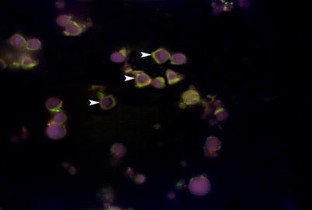

Fig. 1